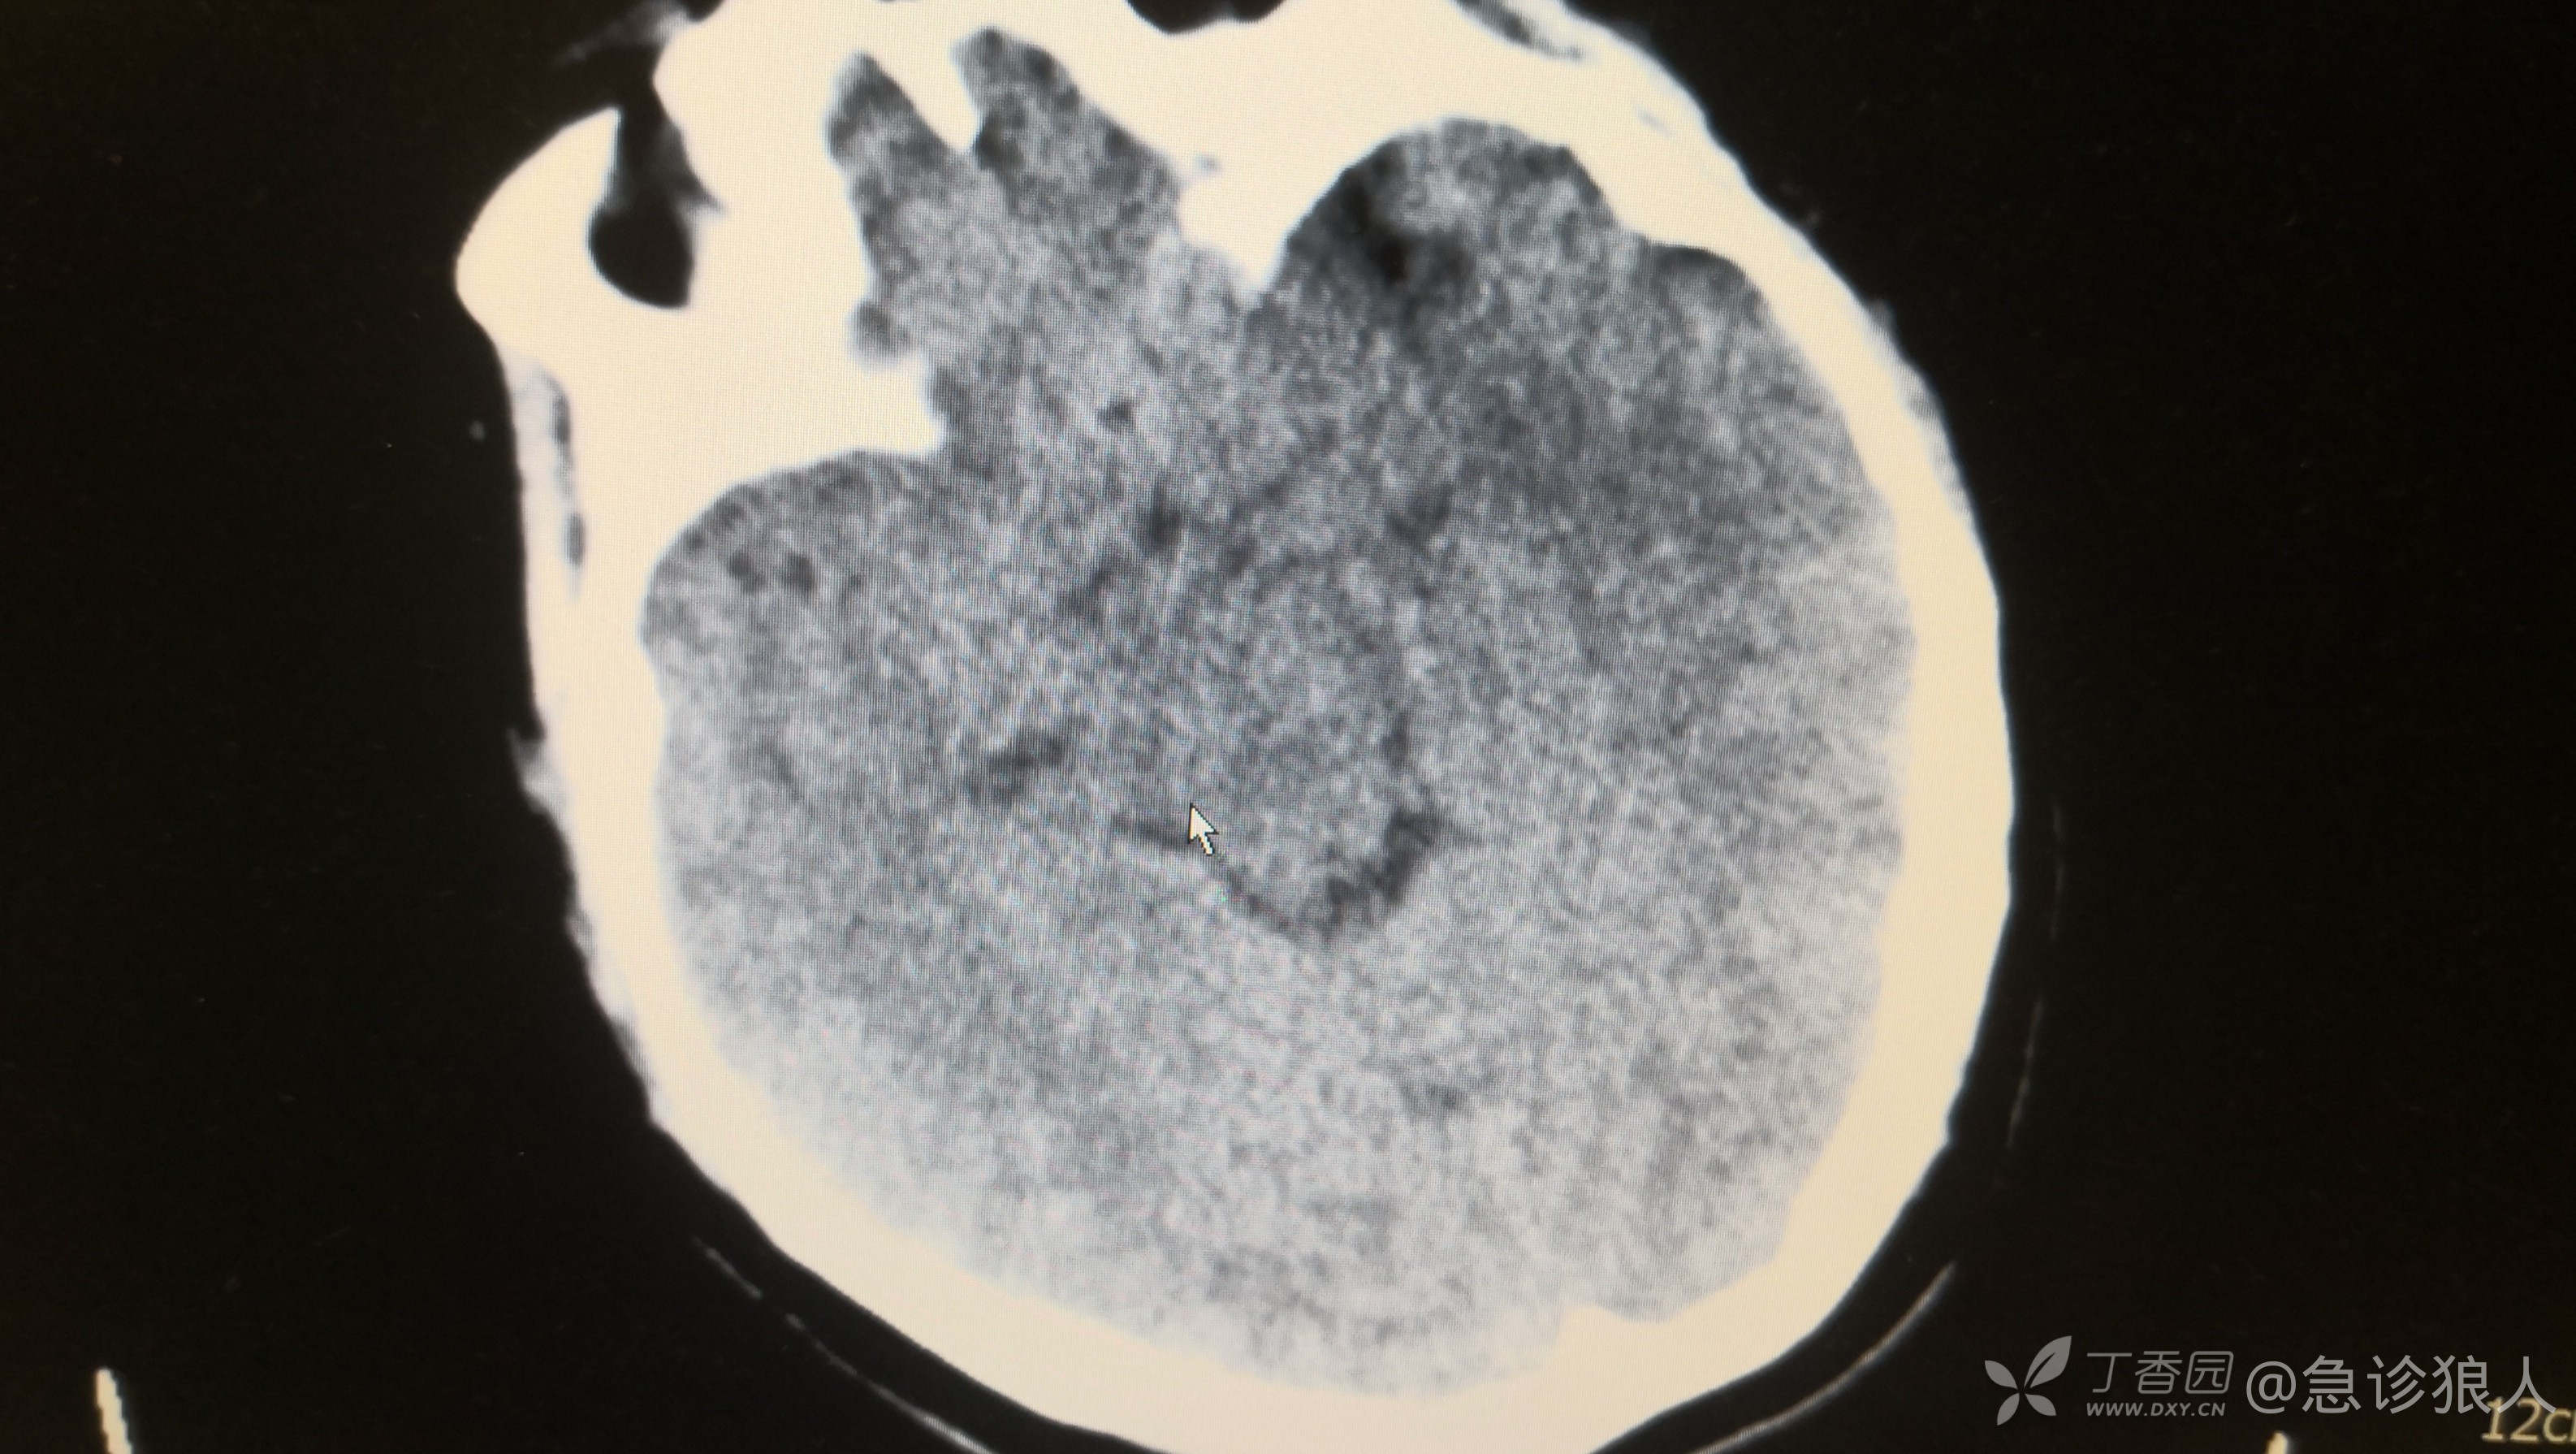

立刻完善颅脑CT,自己排查脑出血、脑梗,再请神经内科会诊。没办法不是!

CT如下

我能看出来的除了颅脑很饱满,看不出来其他的。

这,为啥脑出血CT看不出来,我又反复看了ct确实看不出来。

为啥CT上看不出来呢?